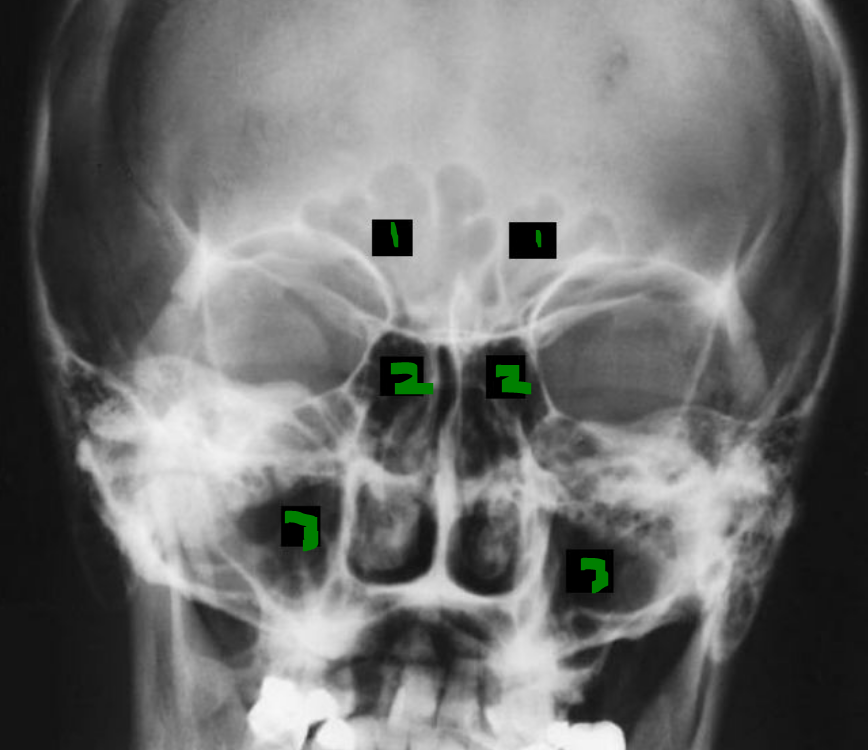

What is 2?

PA Radiograph:

F = frontal sinus

E = ethmoid sinus

M = maxillary sinus